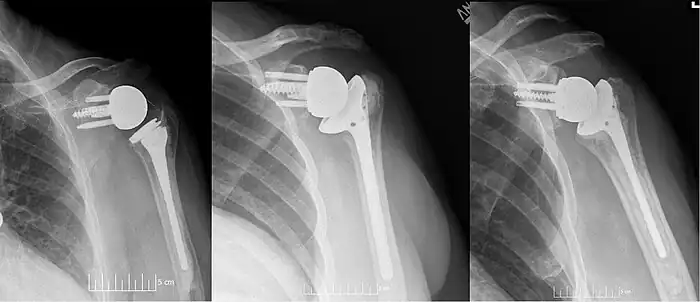

![]() Radiografía simple en vista anteroposterior (AP) del estado de un hombro derecho tras una artroplastia inversa de hombro utilizando una prótesis con centro de rotación lateralizado. | ||